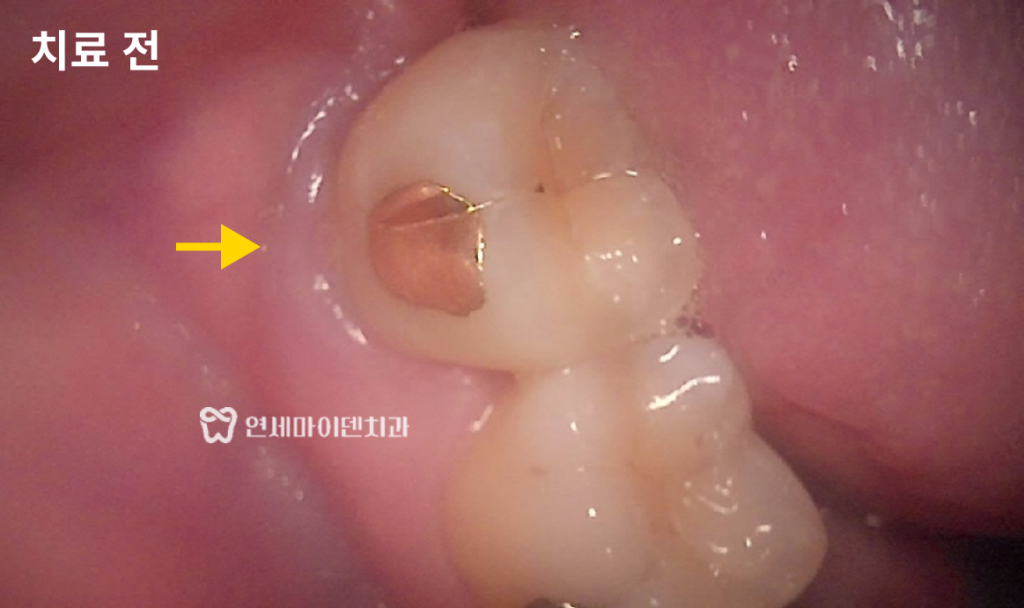

보철물을 제거한 후 내부를 들여다보니

육안으로도 명확한 크랙 라인이 확인되었습니다.미세현미경을 통해 크랙이 치근 방향으로

깊게 내려가있는 것을 확인할 수 있었고뿌리까지 금이 간 수직치근파절의 경우

발치 후 임플란트가 필요한 상황이었습니다.안타깝게도 말씀드렸던 가능성 중

두번째인 크랙 치아의 경우였기 때문에빠르게 발치 즉시 임플란트를 식립하기로 했습니다.